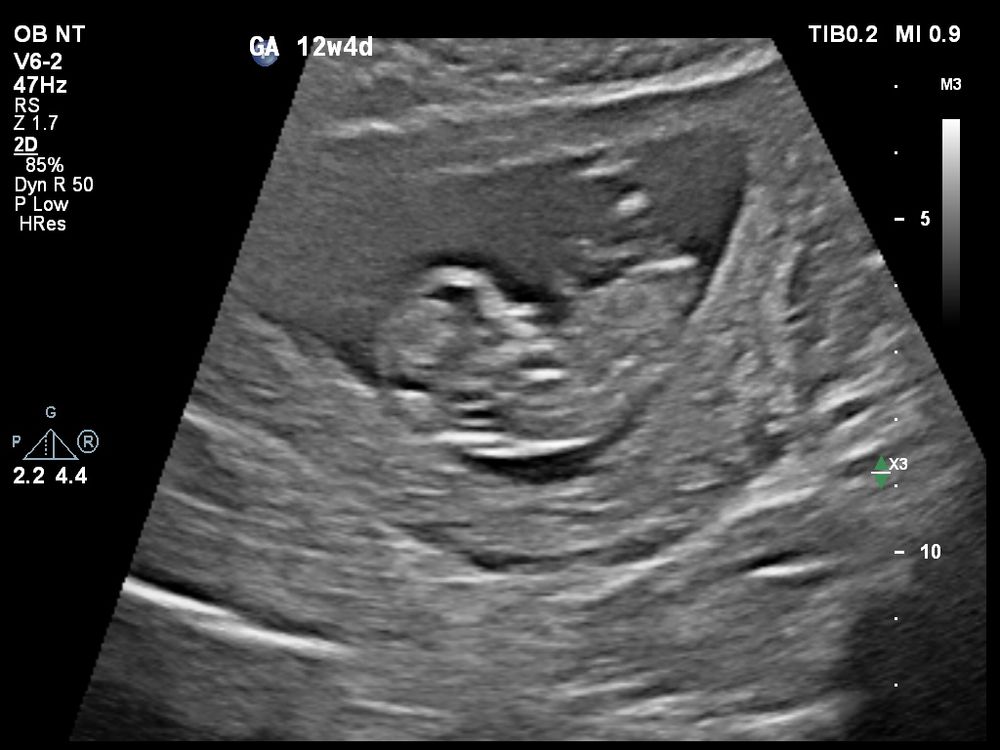

Сегодня сходили с молодым человеком на свидание с лялей 😊 Все у неё/него хорошо, показал(а) нам как плавает, ножки задирает (1 фото). Во время УЗИ мне показалось, что половой бугорок прямо смотрит, надеялась, что на видео/фотографиях все отмечено, а что-то как-то нет, наверное, не в настроении на фотографии был(а) 😀😅

По первым УЗИ (и по овуляции) сегодня срок 12+1, а по скринингу срок 12+5 (6.2см)😅